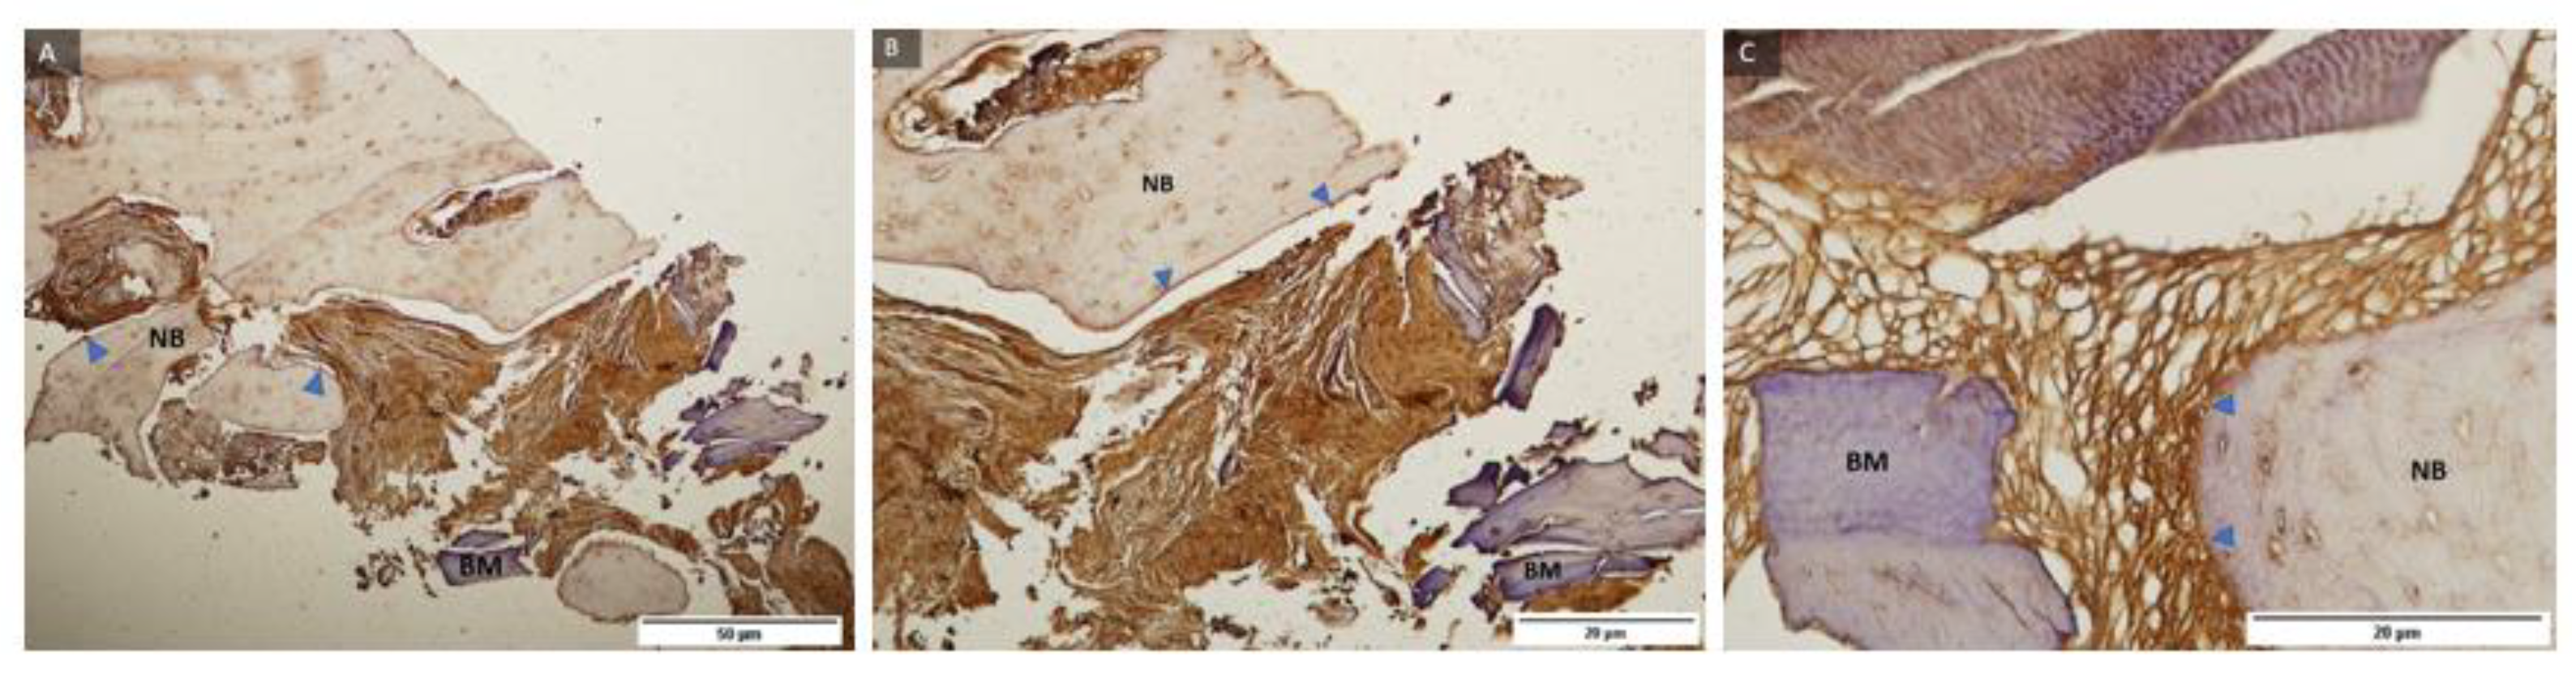

2.4. Immunohistochemical Analysis